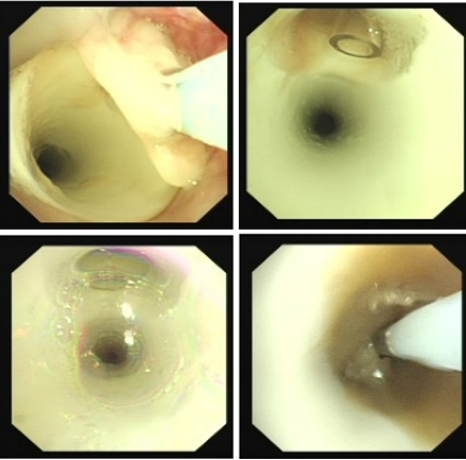

良性中心气道狭窄分为结构性和动力性(6种类型),结构性狭窄包括:管腔内生长(1型),外源性压迫(2型),瘢痕孪缩(3型),扭曲变形(4型);动力性狭窄包括:气道膜部向内膨出(5型),气道软化(6型)。对于动力性狭窄,应考虑用力呼气时的状态,通过操作者的判断,定出最合适、最接近的狭窄程度。治疗方法的制定不仅与气道狭窄程度和长度有关,还与是否存在狭窄过渡段有关。狭窄长度的计算应包括过渡区域。良性气道狭窄形态学分类的诊断方法应通过支气管镜所见及放射学检查来确定。每一个狭窄都可以用4个数字来表示,分别代表部位、类型、狭窄程度、狭窄长度。如:1344代表声门下瘢痕性挛缩性狭窄、狭窄程度>75%、狭窄长度>5 cm,这是一种非常难以处理的良性气道狭窄;2311代表气管瘢痕性蹼状网眼狭窄、狭窄程度<25%、狭窄长度<1 cm,这是一种比较容易处理的良性气道狭窄。热消融技术(APC、电凝、激光)是治疗增生性气道腔内病变(如良性肿瘤和单纯肉芽)的简单、快速的方法。但在治疗瘢痕狭窄病变时,其本身可对气道造成更重、更大范围的损伤,引起更为严重的肉芽组织增生和瘢痕形成,从而导致复发率高,且治疗次数的增加可导致狭窄病变范围增大并最终破坏软骨,导致气道塌陷,使患者彻底失去治愈的机会。电凝和APC仅适合管腔内生长的1型良性中心气道狭窄,并不适合其他类型良性中心气道狭窄的治疗。即便如此,基底部的处理也应避免使用此类治疗方法。针形电刀与气道黏膜接触面极小,不会造成损伤面扩大,瘢痕性气道狭窄的治疗宜选用针形电刀进行切割、松解。因激光也有切割的作用,因此也可选用激光治疗,钬激光、铥激光控制烧灼深度最浅可达0.4 mm,因此更适合良性瘢痕增生性气道狭窄的治疗。冷冻治疗分为冷冻切除(简称冻切,cryoextraction)及冷冻消融(简称冻融,cryoablation)。对于腔内生长的病变可采用冻切治疗,由于容易出血,其安全性不如热消融技术。对于瘢痕病变,冻切技术无法实施,则采用冻融治疗,冻融治疗不促进肉芽组织增生。与热消融相比,冷冻不易导致软骨损伤。通常在热消融治疗接近气道壁时或球囊扩张后采用冻融治疗处理剩余病变,有利于减轻瘢痕再狭窄发生的速度与程度。严重气道狭窄在开通气道前不要使用冻融,因其可引起气道水肿,加重气道狭窄,从而导致窒息。因此,冻融治疗后肺部体征监测及气管镜复查十分重要。机械扩张技术包括球囊扩张和硬质支气管镜扩张,并发症有气道撕裂、再狭窄、出血。(1)球囊扩张:是治疗瘢痕性气道狭窄最主要的技术,其优势是患者治疗后无明显的狭窄段延长,狭窄复发时再狭窄的程度比热消融治疗后轻得多,有利于维持气道复张的疗效。对气管黏膜损伤小,可以在软镜下应用,但需要中断通气。对于挛缩、韧性较强的瘢痕,可先用针形电刀进行切割以松解瘢痕;避免直接暴力球囊扩张,导致气道膜部的撕裂伤。(2)硬质支气管镜扩张:其优势是扩张时不需要中断通气,安全性更好。针对瘢痕肉芽组织增生导致介入治疗后的气道再狭窄,可采用气道狭窄部位局部应用药物的方法抑制瘢痕肉芽组织增生。介入治疗后气道再狭窄可选择的治疗药物有:糖皮质激素、丝裂霉素C、曲尼斯特、紫杉醇等。通过直接植入放射性物质(最常用铱-192)或经过可弯曲支气管镜近距离照射气道瘢痕肉芽组织,促使成纤维细胞凋亡。气道支架置入首选硅酮支架,禁用金属裸支架。支架治疗应作为良性气道狭窄最后选择的治疗技术,启动气道支架治疗的指征:①应用前述各种治疗方法疗效不佳,不能维持气道通畅;②在确定外科手术前临时放置;③外压性气道狭窄;④气道软化、塌陷且无法或不准备行外科手术治疗。病例1:17岁,女性,骨折术后肺炎插管,拔管后(2月14日)气道明显狭窄(图3)。2月15日评估:HR 113次/min,R 24次/min,静息下SpO2 97%(FiO2 50%),咳嗽及说话后喘鸣,有阵发性血氧下降。会诊后拟行急诊介入治疗。2月15日无痛气管镜示:声门下腔黄色及乳白色膜状坏死物,气管上段大量黄色坏死物并管腔重度阻塞,仅见小孔,以冷冻法清除坏死物后管腔通畅(图4)。术后气促明显改善,无需吸氧。病例2:77岁,女性,呼吸困难2个月,加重3天,于2023年12月2日入院(2023年9月气管插管,插管后20余天后拔管)。入院当天查体:HR 125次/min,R 30次/min,静息下SpO2 96%(高流量FiO2 30%),PaCO2 56 mmHg。患者术前影像如图5所示。12月3日查体:HR 140次/min,R 35次/min,BP 190/90 mmHg,SpO2 68%~75%(FiO2 100%),躁动不安,急查血气分析:PaCO2 89 mmHg。紧急床旁无创通气支持下气管镜:气管上段狭窄80%以上,较多黄白黏稠分泌物在狭窄口随呼吸摆动,予抽吸后SpO2升至98%,见狭窄处直径约3 mm,外径5.2 mm,软镜无法进入,遂置入导丝,10#球囊扩张多次,狭窄部位增宽,外径4 mm气管镜引导6.0号气管导管经口插管成功(图6)。插管后患者HR 98次/min,复查血气分析示PaCO2 41 mmHg,氧合指数300 mmHg以上。12月4日气管镜示:右鼻旁路进镜,缓慢退气管导管至声门,距声门3 cm处狭窄,直径7 mm,予12#球囊扩张1 min,2次,未见出血,扩张后直径约12 mm,地塞米松局部保留,气管导管复位(图7)。12月5日拔除气管导管。12月6日气管镜示:气管上段瘢痕狭窄(管径10~12 mm),少许膜状坏死、未见肉芽,予以清除坏死物,7点、11点冻融,术毕注入地塞米松5 mg(图8)。12月13日气管镜示:气管上段瘢痕狭窄(管径12 mm左右),少许膜状坏死、未见肉芽,予以清除坏死物,7点、11点冻融,术毕注入地塞米松5 mg(图9)。